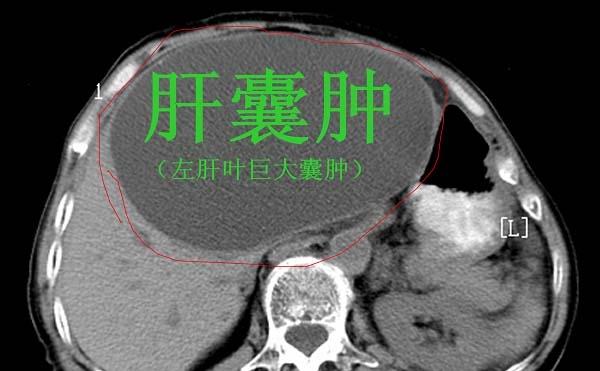

肝囊肿是最常见肝脏结节,肝囊肿的原因并不是特别的清楚。简单来说,肝囊肿就是肝里面有一个包块,包块里面是水。肝囊肿可以是单发的,也可以是多发的。如果肝囊肿没有症状,直径小于5厘米,不需要处理,定期复查即可。如果肝囊肿不断变大,出现不舒服,压迫周围组织,可以做手术。现在肝囊肿一般都是微创手术,腹腔镜下开窗引流,把囊液引出来就可以了,但是肝囊肿容易复发。还有一种遗传性疾病,肝脏和肾脏多发的囊肿,肝上面有十几个甚至几十个囊肿。对于这样的患者,平时一定要定期复查,注意保护肝功能,因为后期可能出现肝衰竭,甚至要做肝移植手术。